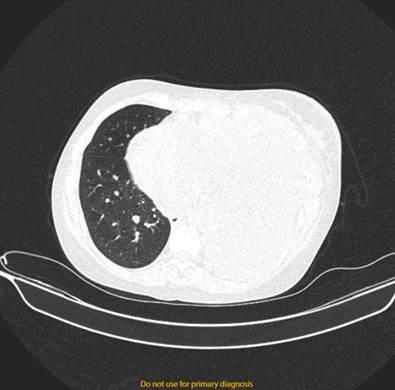

Figura 4: TAC simple de tórax se observa, se observa asimetría de campo pulmonar, con colapso de pulmón izquierdo, con atelectasia.

Imagen tomada de: Caso Clínico Clínica Abendaño.  Loja - Ecuador

El estudio radiológico por medio de una TAC simple mostró tejidos blandos y elementos óseos que integran la pared, sin evidencia de alteraciones. Se visualiza adenomegalias en el nivel IV izquierdo de 27 mm, otras imágenes ganglionares más pequeñas de entre 9mm. Aorta, troncos supra aórticos y arterias pulmonares impresiona de calibre normal. (Fig. 4) Llama la atención masa mediastinal anterior isodensa al músculo, que desplaza las estructuras mediastinales hacia la derecha, mide aproximadamente 19,6 x 12 x 10 cm. Corazón de tamaño y morfología normal. Con ventana de pulmón se observa campo pulmonar izquierdo colapsado, el derecho no se observa zonas de infiltrados ni consolidación. Derrame pleural izquierdo, con presencia de tabicaciones en su interior, volumen aproximado de 2000cc.